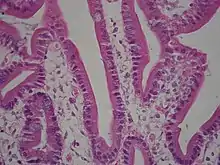

Under microscopy, the duodenum has a villous mucosa. This is distinct from the mucosa of the pylorus, which directly joins to the duodenum. Like other structures of the gastrointestinal tract, the duodenum has a mucosa, submucosa, muscularis externa, and adventitia. Glands line the duodenum, known as Brunner's glands, which secrete mucus and bicarbonate in order to neutralise stomach acids. These are distinct glands not found in the ileum or jejunum, the other parts of the small intestine.[10]: 274–275

Dog Duodenum 100X

Dog Duodenum 100X Duodenum with amyloid deposition in lamina propria

Duodenum with amyloid deposition in lamina propria Section of duodenum of cat. X 60

Section of duodenum of cat. X 60

Duodenum with brush border (microvillus)

Duodenum with brush border (microvillus)

The villi of the duodenum have a leafy-looking appearance, which is a histologically identifiable structure. Brunner's glands, which secrete mucus, are only found in the duodenum. The duodenum wall consists of a very thin layer of cells that form the muscularis mucosae.